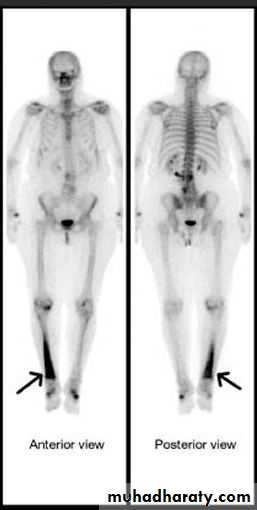

The TC 99m radionuclide bone scan and MRI show changes much earlier.

a radionuclide bone scan will show increased activity both on the early ( blood pool ) images reflecting hyperaemia and on the delayed bone phase images.

Bone scanning is positive in both osteomyelitis & malignant tumour and can not be used in differentiation .

A radionuclide bone scan is much more sensitive for detecting metastases than plain film .